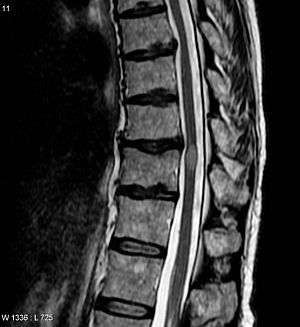

| An MRI showing a transverse myelitis lesion (the lesion is the lighter, oval shape at center-right), this MRI was taken 3 months after patient recovered | |